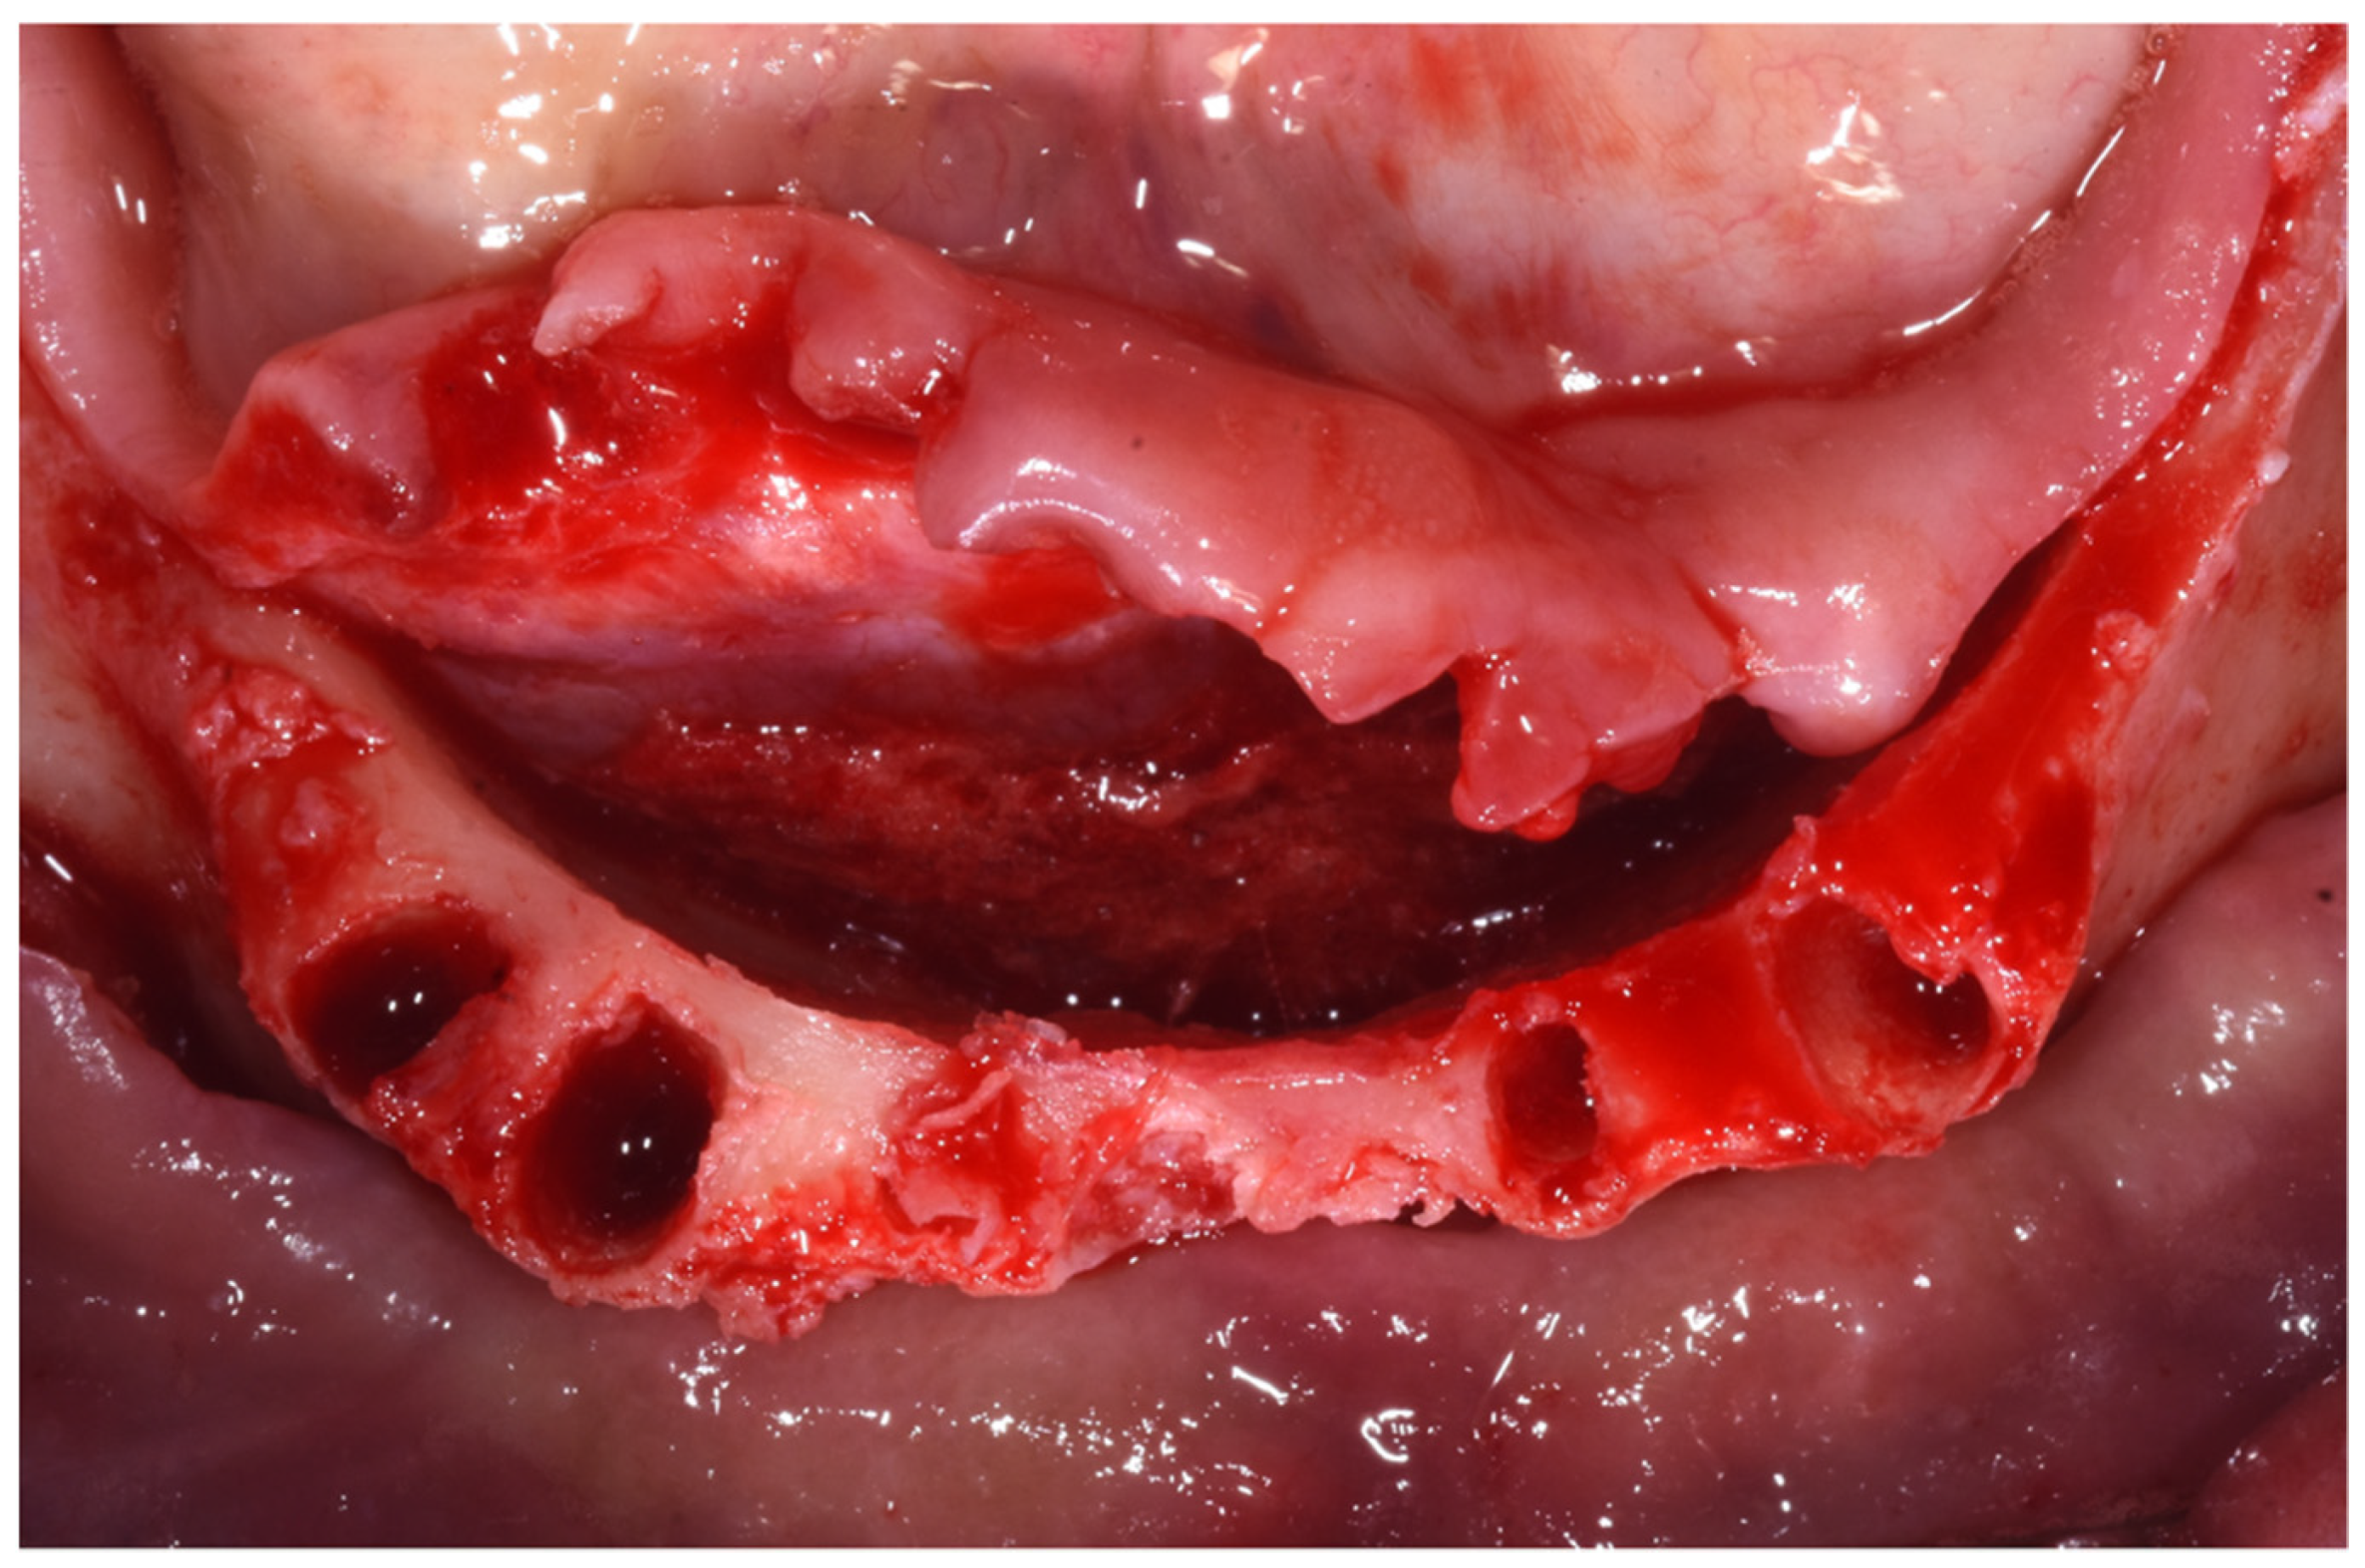

2. Case Report

Surgery Appointment